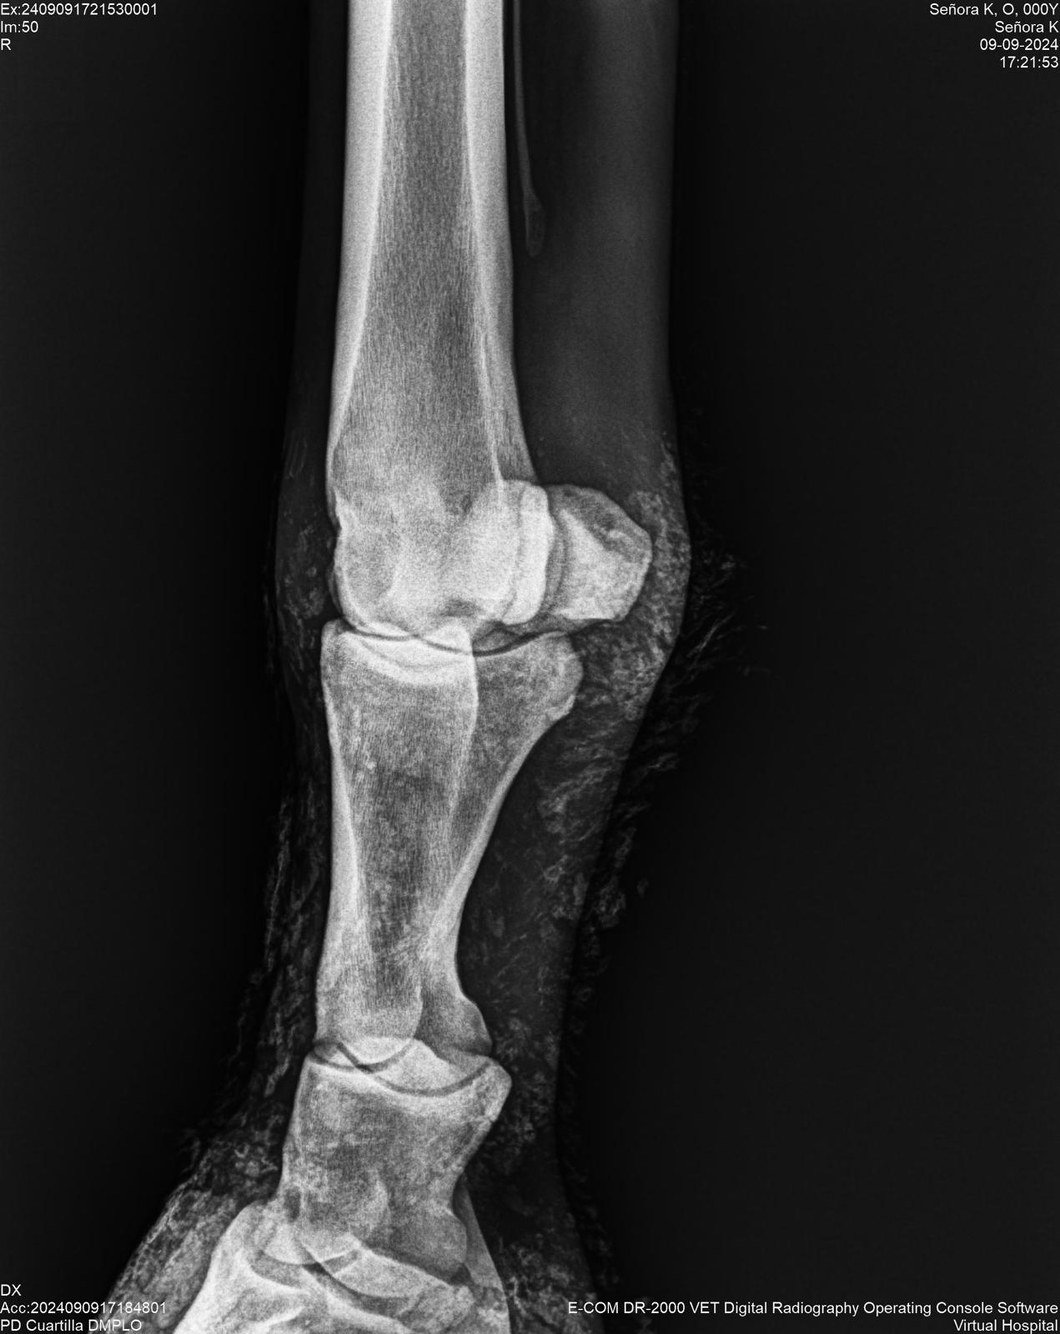

LOTE 44, SEÑORA K

Identificador: #291147-

Generacion 2022